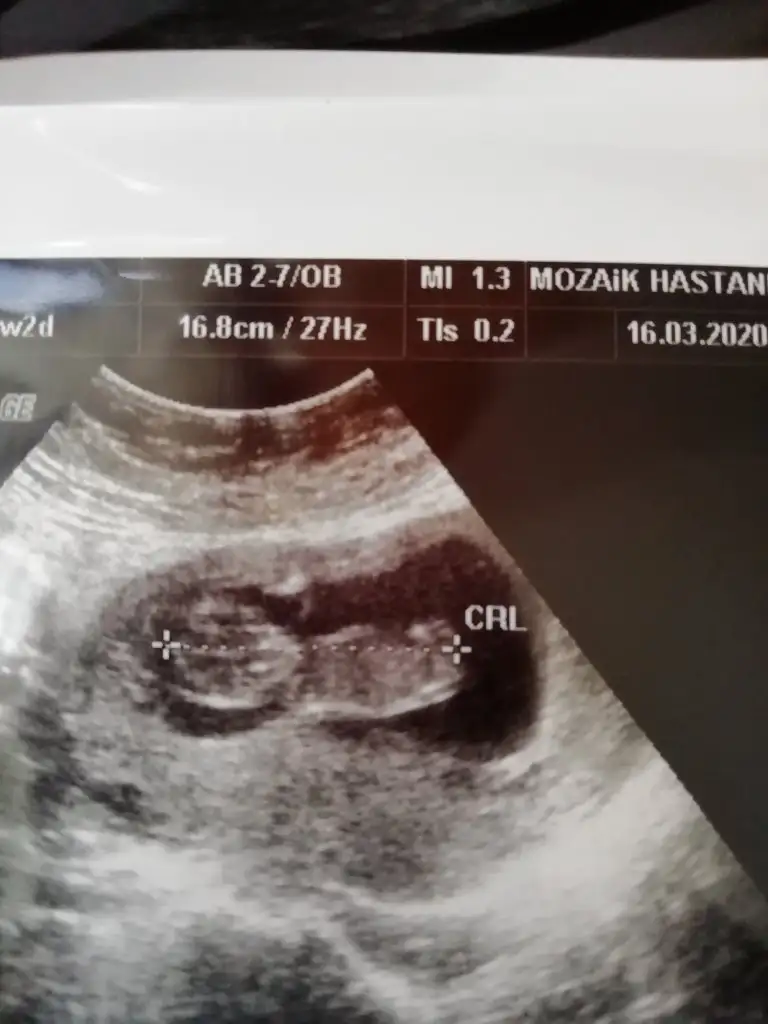

Merhaba yeni uyeyim elimde 7 haftalik karindan 10 haftalik alltan ulturason goruntusu var cinsiyet tahmini yapabilirmisiniz acaba şimdiden teşekkurler ilk resim 7 hafta karin son resim 10 haftta altan bakildi.

Eklentiler

• 20200302_104601.webp

20200302_104601.webp

10,3 KB · Görüntüleme: 50

• 20200317_132838.webp

20200317_132838.webp

26,2 KB · Görüntüleme: 50

Dr da erkeğe benziyor çıkıntısından dedi anketinizi yollar mısınız oylayayım 😊